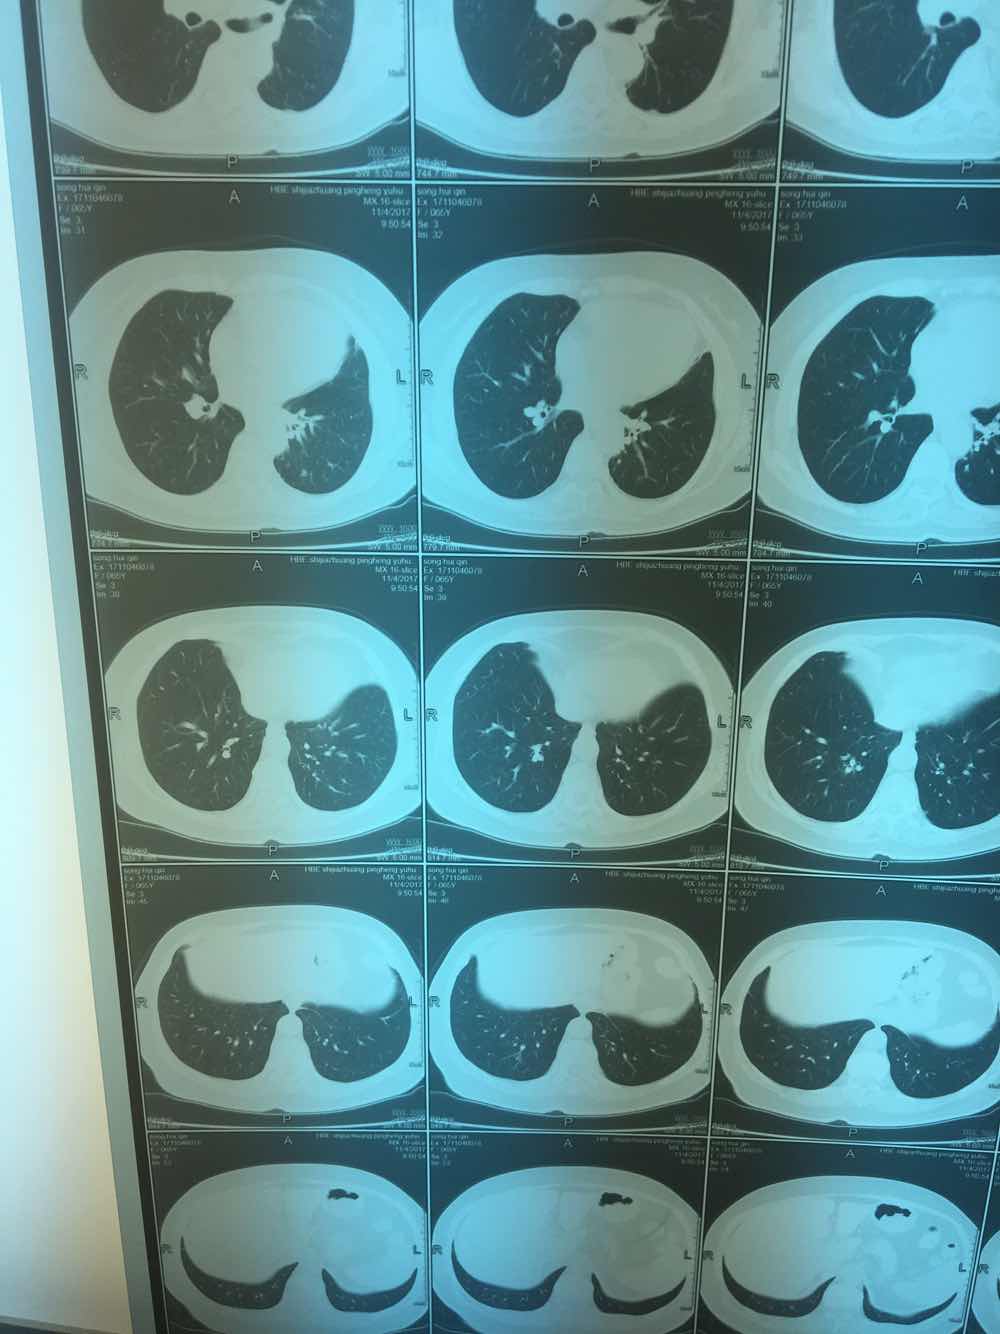

先看第一位患者,简称月半弯。她因为发现肺里面有磨玻璃影,咨询陈医生。磨玻璃影如图所示。

陈医生问完病情后,建议她直接手术。

再看第二位患者,简称希望,大家看她的图跟第一位患者的几乎如出一辙,但陈医生第一次却只建议她定期复查

她们两位提供的病灶,都可以称为磨玻璃影,就像玻璃上被砂纸磨过,留下很粗糙的一片。

同时邻近胸膜的地方,都有点牵拉,就是胸膜局部有牵拉出一点。

大家仔细看一下两位的胸膜牵拉,月半弯的比较锐利,拉扯出来的部位呈三角形。而希望的片子里,拉扯出来的部位没那么锐利,绝呈一点不规则的方形。

大家都知道,这个蛇的头要是三角形啊,毒蛇的可能性就越大。月半弯觅友的胸膜牵拉部分锐利,呈三角形。更重要的是,月半弯觅友曾经有过乳腺肿瘤的病史,所以陈医生建议她直接手术了。

而希望觅友的胸膜牵拉呢,则比较接近方形,最重要的是,没有症状,体检发现的。所以陈医生最初建议她定期复查。